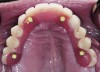

This technique, which offers the advantage of being retrievable and avoids the biologic complications of cement-retained restorations, can also be used successfully for multiple restorations (Figure 5 and Figure 6).

For a large-span or full-arch provisional prosthesis on immediate-load cases, a cement-retained prosthesis must be cemented with a definitive cement; if temporary cement is used, it can wash out, inducing micro movement during the early stages of osseointegration and cause implant failure. If definitive cement is used, the retrieval of the interim restoration is compromised, and no further adjustment can be made. Screw-retained provisionals for full-arch cases with immediate load or delayed load are preferred (Figure 10).

Figure 5. Multiple splinted units with palatal access screw.

Figure 5

Figure 6. Final restoration.

Figure 10. Immediate-load maxillary arch. The prosthesis is screw-retained.

Figure 10